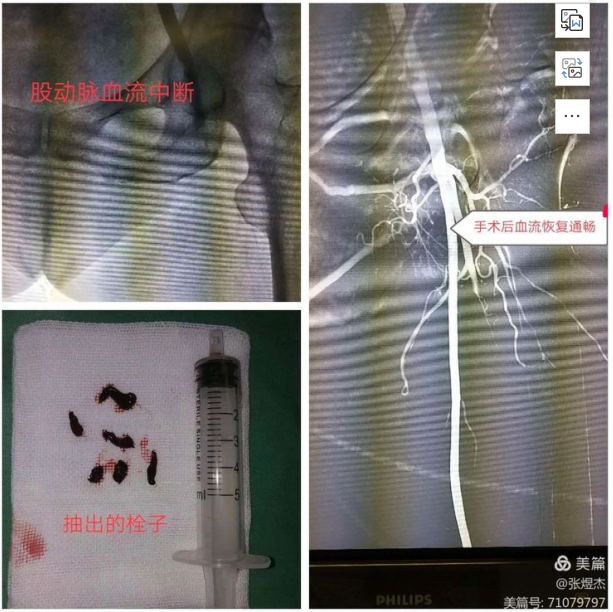

这时候真正的危害血栓栓塞就会随之而来,这些栓子如果堵塞脑动脉那就会造成严重并发症急性脑梗死;如果堵塞下肢动脉那就会造成足部急性缺血甚至坏死。下面这个病例就是乌海市人民医院介入血管外科过年期间收治的一名房颤突发下肢动脉栓塞的中年女性患者,当时足部皮肤已经出现缺血发绀表现,患者疼痛感明显。

手术在凌晨4点立即开始,通过一个多小时的介入微创手术,抽出许多堵塞动脉的栓子后,足部血供重新恢复,患者凉麻疼的感觉逐渐好转,避免了足部因血管堵塞进一步缺血坏死导致截肢的结果。